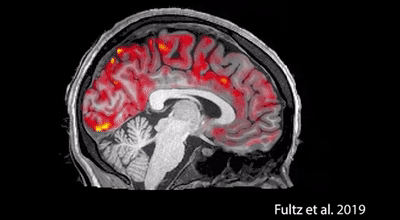

给大家看一个动画,这是波士顿大学刊登在科学杂志上的一份报告

它们拍下来人睡眠时候的,大脑对自己的“洗脑”的过程,当你睡着了以后,红色的血液会周期性流出大脑,蓝色的脑脊液趁机涌入,清除毒素,包括导致阿尔兹海默症(俗称老年痴呆症,但并不完全等价)的β淀粉样蛋白,而这只有在睡觉时才能实现。

如果你在熬夜,脑脊液是没办法涌入清除毒素的,因此长时间睡眠不够是真的会让你越来越笨的。